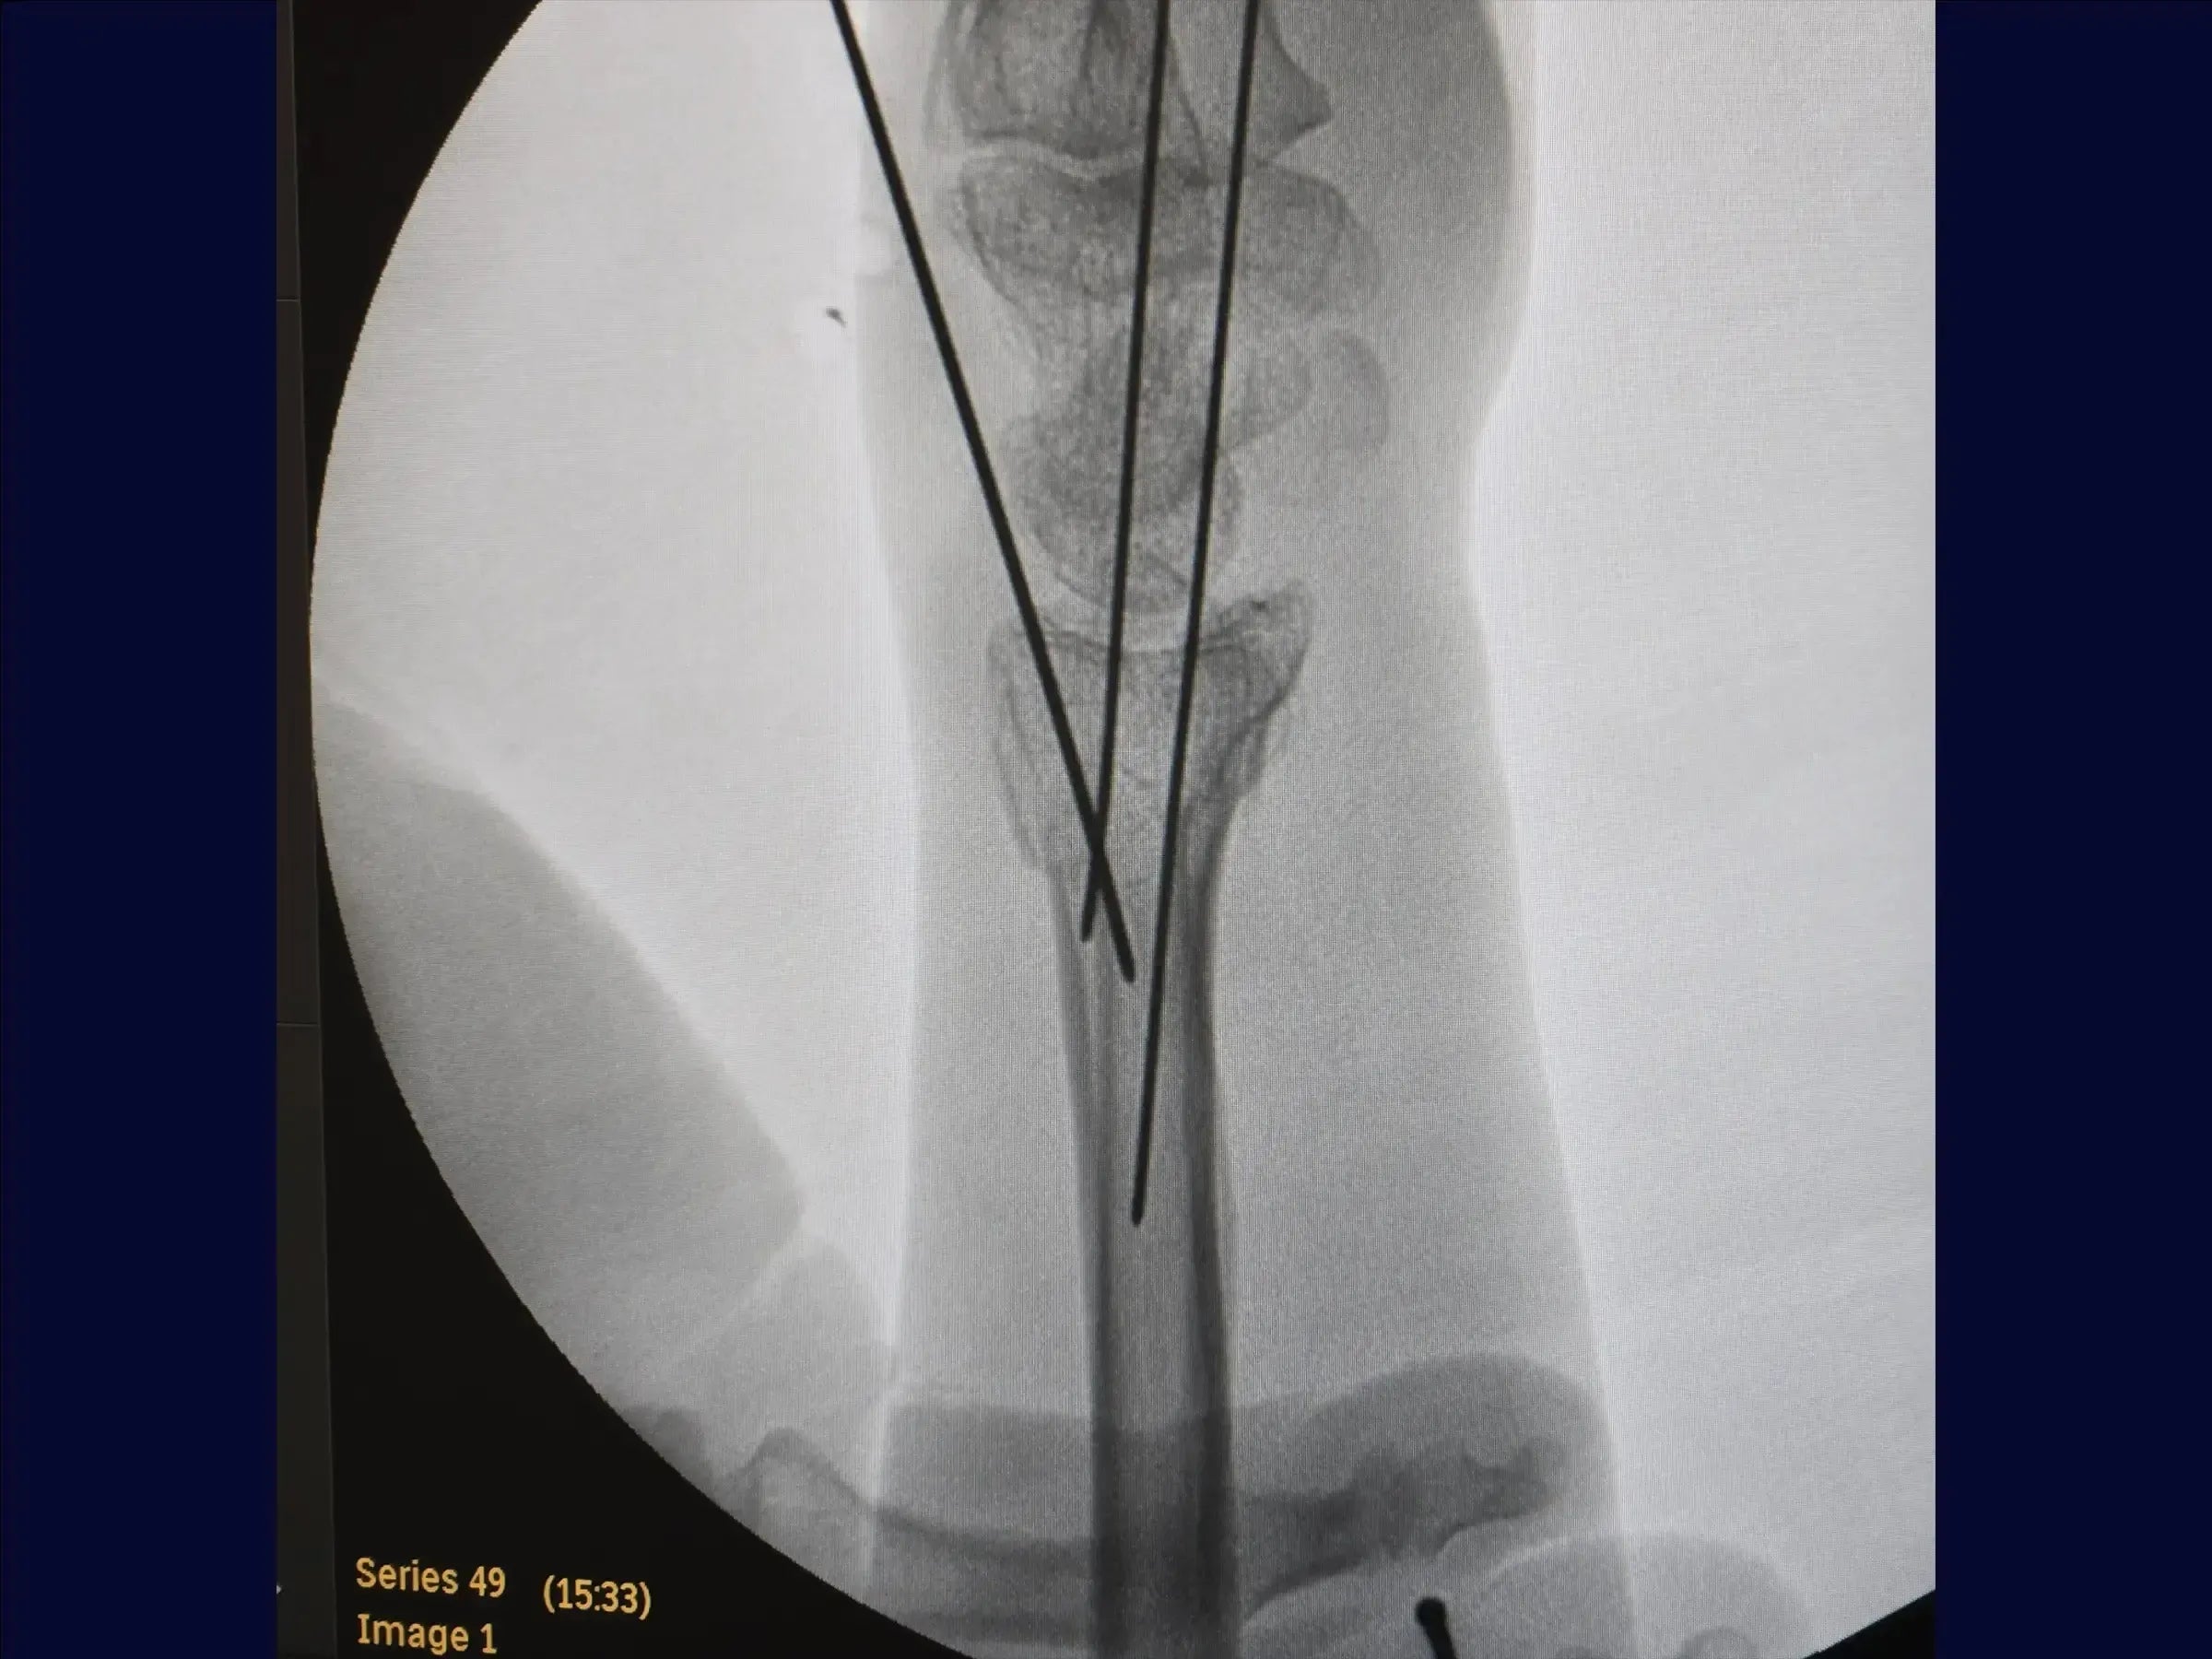

- Evaluación y reducción provisional: La formación abarca el análisis de imágenes de fracturas multifragmentarias del radio distal y la reducción por tracción manual ( ligamentotaxis ). Incluye la fijación percutánea provisional con alambres a la estiloides radial y al tubérculo de Lister para estabilizar los fragmentos.